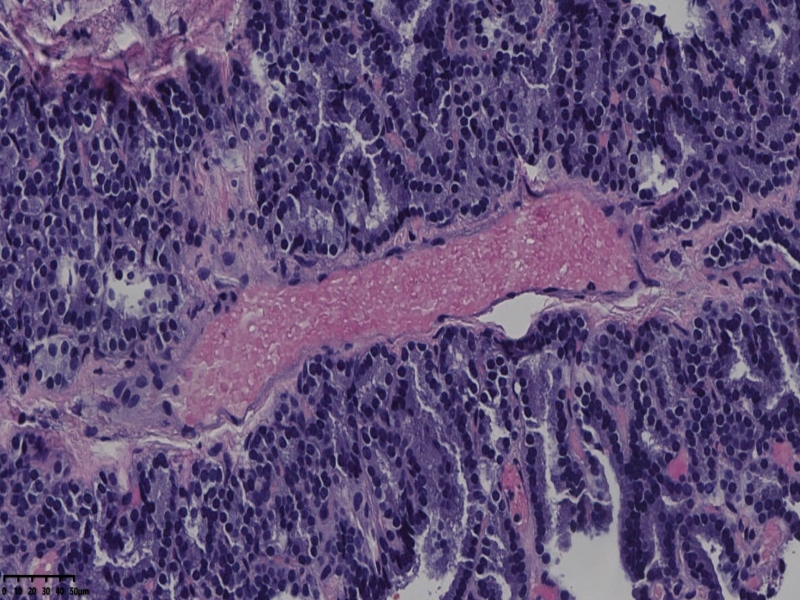

男、69、甲状腺左叶肿物,部分为囊性,囊内可见乳头状结构,上皮核重叠,没有核沟,没有毛玻璃样改变,没有核内假包涵体。255427

部分区域瘤组织与周围甲状腺组织分界明显,没有包膜样结构,滤泡结构为主,细胞异型明显。

会诊结果:(左叶甲状腺近峡部)甲状腺肿瘤,考虑为具有RAS核的乳头状癌,建议免疫组化及基因检测。